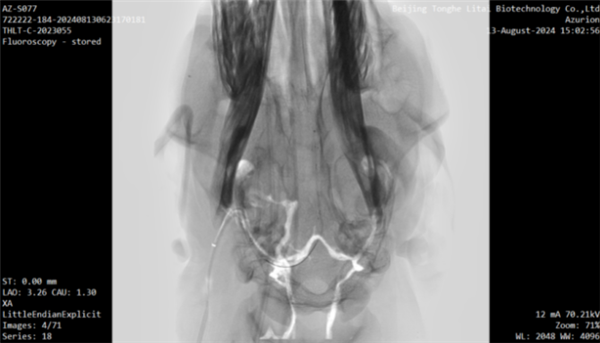

整个手术过程在先进的DSA(数字减影血管造影)技术引导下精准进行,确保了每一步操作的安全无误,彰显了团队在复杂手术操作中的高超技艺与严谨态度。